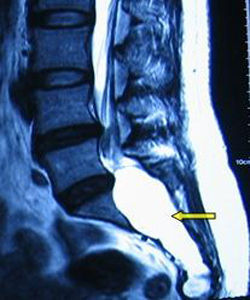

MRI檢查

是診斷椎管內脊膜囊腫最可靠的檢查方法,囊腫呈長條狀囊袋形、卵圓形和不規則形等,囊液信號與腦脊液信號相似,TlWI呈低信號,T2WI呈高信號。IB型位於骶管內,與硬脊膜囊之間有脂肪相隔。Ⅱ型位於硬脊膜囊側方,囊內有神經根存在。

CT及MRI特點骶管囊腫因其位置的特殊性,臨床表現又與其他椎管內疾病相似而未引起人們的重視,CT掃描腰椎間盤不容易注意骶管情況而漏掃,除非骶管囊腫引起明顯骶管骨質吸收,CT的密度解析度最高,對囊腫周圍骨質結構的改變顯示最佳,評價囊腫對椎管骨壁的壓迫性骨質吸收優於MR,若結合增強掃描,亦能大致確定囊腫的性質;但是由於受骨偽影及解析度的影響,腫瘤與周圍組織的關係在CT上顯示欠清晰,由於M R I對水的敏感度很高,囊性病灶的診斷中,C T不及MRI;MRI因其無創,軟組織分辨力高,多方位成像又無骨偽影,能較好顯示囊腫大小、數目、分布、內部結構其與周圍組織的關係,其MRI表現:

骶管囊腫(1)囊腫位於骶管內,呈卵圓形,串珠狀及不規則形,可以單發或多發。(2)囊腫境界清楚,囊壁菲薄,信號與腦脊液相似,T1W I呈均勻一致的低信號,T2WI呈均勻的高信號,增強掃描囊壁及囊液無強化。(3)囊腫主要位於骶1-3椎平面骶管內。

MRI脊髓造影: MRI脊髓造影具有成像迅速、無創傷性,只要通過增強腦脊液的信號,無需造影劑便可獲得高反差的圖像,經三維重建後的圖像克服了腰椎生理彎曲的影響,獲得包括腰骶部冠狀位在內的各方點陣圖像,結合常規矢狀位和軸位的圖像,能替代傳統的脊髓造影檢查,提供腰骶部硬脊膜外腔、神經根及神經根鞘的影像學表現,可為臨床準確地診斷腰骶部神經根腫瘤提供客觀的影像學依據。Masato Tanakaa認為:閥門機制對囊腫的形成可能起重要作用,MRI脊髓造影中如果出現充盈缺損陽性現象是一個很好的評價是否手術的指標。